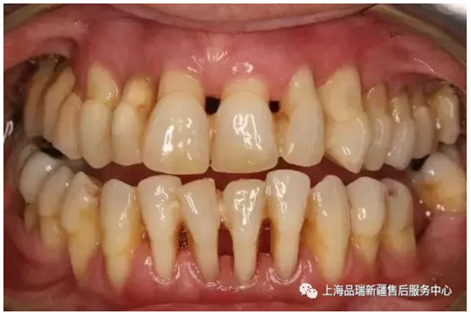

4.png

其實牙結(jié)石這玩意兒賊能傷害牙齒。

在還是牙菌斑的時候,就能導(dǎo)致蛀牙以及其它各種牙周疾病比如牙齦出血等;等進(jìn)化成牙結(jié)石后,更是容易吸收大量細(xì)菌毒素,引起牙周炎癥、牙齦水腫出血,最終導(dǎo)致牙齦萎縮,牙齒松動脫落。